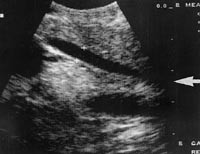

Laparoskopisk ultralydundersøkelse ble utført hos 441 pasienter (fig 2). På grunn av mistanke om stein i de dype galleganger ble ERCP utført hos 147 pasienter. Stein ble påvist hos 72 av pasientene (49 %), og hos samtlige ble det utført papillotomi med steinekstraksjon.

Tilfredsstillende ultrasonografisk fremstilling av galleveiene ble oppnådd hos 377 pasienter (86 %). Hos de resterende fikk vi ikke optimal fremstilling av den intrapankreatiske del av gallegangen.

Vi påviste choledochusstein ved laparoskopisk ultralydundersøkelse hos 29 av pasientene (7 %), og av disse hadde 18 (12 %) fått utført preoperativ ERCP. Hos de øvrige 11 pasientene (4 %) forelå det ingen preoperativ mistanke om choledochusstein.

I vårt materiale ble det påvist choledochuskonkrement hos 29 pasienter (7 %) (fig 4). Av disse hadde 18 (12 %) gjennomgått preoperativ ERCP. Det er kjent at tidsintervallet mellom ERCP og laparoskopisk kolecystektomi er av betydning for påvisning av gallegangskonkrement. Det ideelle er å operere pasientene umiddelbart etter den endoskopiske prosedyren for å minske faren for gallegangskonkrement.